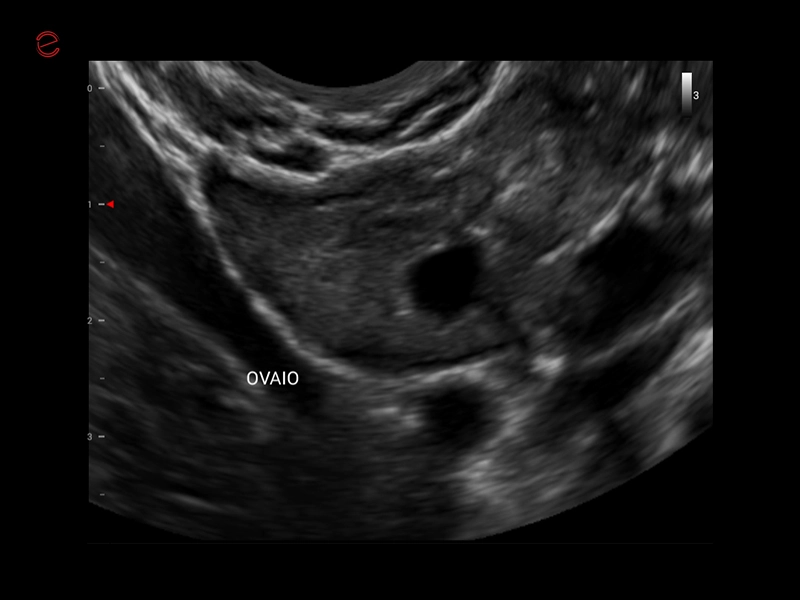

MyLab™X1 Go - WH Ovary

MyLab™X1 Go - WH Ovary